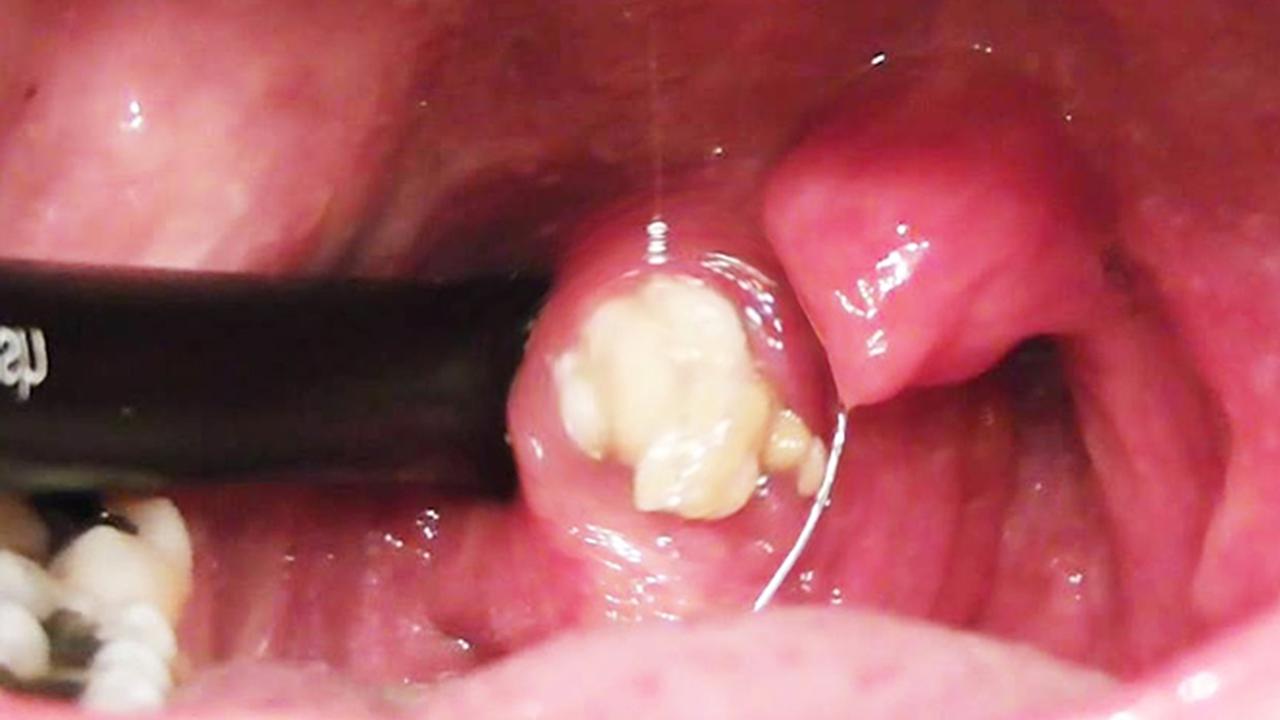

Liputan6.com, Jakarta Bila melihat ada bercak putih kekuningan yang tampak seperti batu di amandel, itu disebut tonsil stone. Dalam istilah lain disebut tonsilolith dan para dokter spesialis telinga, hidung, dan tenggorokan (THT) biasa menyebutnya detritus.

"Tonsil stone ini merupakan kumpulan dari sel lekosit (bakteri), sel mati, epitel, dan sisa makanan yang kemudian berkumpul menjadi banyak dan mengeras sehingga terlihat seperti batu berwarna putih kekuningan," tutur dokter Hably Warganegara, SpTHT-KL dari RS Khusus THT-Bedah KL Proklamasi, Jakarta.

Kondisi ini paling sering dialami oleh mereka yang mengalami infeksi amandel berulang. Hal tersebut terjadi karena ketika infeksi, tonsil akan melebar sehingga bakteri, sel mati, epitel, dan sisa makanan akan mudah terperangkap di kripta (celah lekukan pada tonsil).